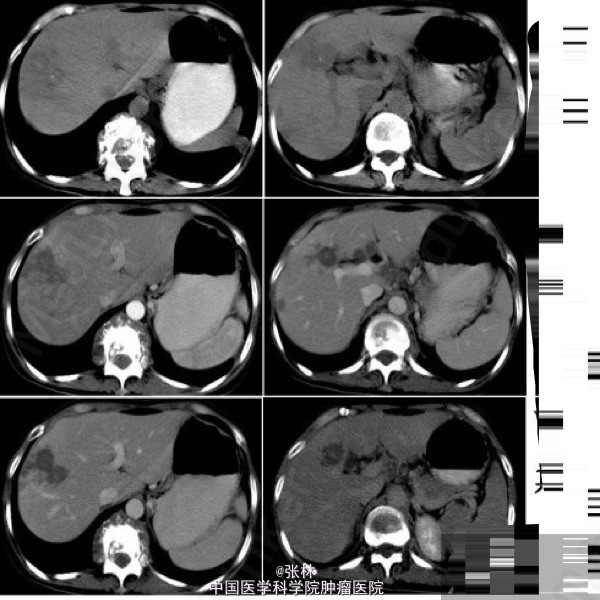

病史:女性,41岁,肝区不适伴反复双肾区疼痛1年。

上腹CT:肝内多发斑片状或类圆形灶状密度异常,占位效应不明显,边界模糊,平扫呈不均匀稍低密度,局部可见点状高密度钙化影。增强扫描:动脉期病变周围正常肝实质可见片絮状轻度一过性强化,病变内部可见强化的小血管影;静脉期病变呈低密度影,内部无明显强化;延迟扫描病变范围缩小,周边轻度强化。 影像检查发现:T10至L1椎体破坏,并冷脓肿形成;左下肺结核。

临床诊断:肝结核、脊柱结核、肺结核。予以规律抗结核治疗。